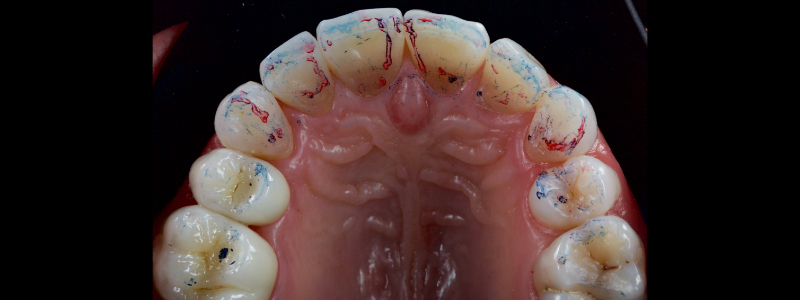

Before polymerization, the contact points are cleared with an Interproximal Carver Long (IPCL) like American Eagle (Fig. 9). The resin mass is then polymerized to create a palatal shell (Fig. 10).

The next step in the Class IV build-up is the realization of an incisal edge halo with either a packable resin on a flat plastic (Fig. 11) or flowable resin on a #1 brush (Fig. 12).